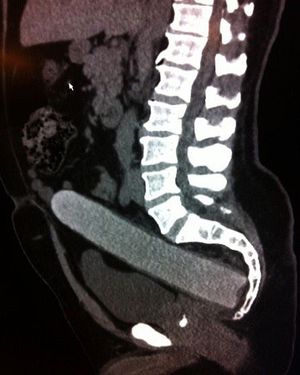

Not too hard to figure out what’s that rectal foreign body! Now to a weirder matter, the majority of cases of rectal foreign bodies are the result of insertion during erotic activity. Typically found objects are vibrators, dildos, light bulbs, candles, shot glasses, and bottles. Some rectal foreign bodies may have been initially swallowed but later present with complications in the rectum. Patients may be very embarrassed to disclose the circumstances regarding the foreign body insertion, and there may have been multiple attempts at self-removal. Typical clinical findings of a rectal foreign body are pain with defecation, abdominal pain, rectal bleeding, pruritus, and constipation. Delays in seeking medical attention and multiple attempts at self-removal can lead to mucosal edema and muscular spasms, making removal of the object more difficult. Photo by @drcellini